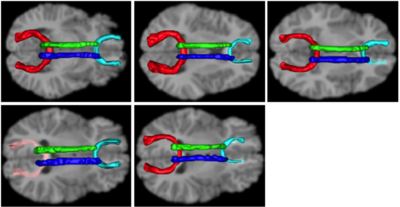

from the atlas to each individual. Automatically segment white matter tracts and quantify diffusion properties using volumetric pathway analysis.

Tracts on each of the individual cases.